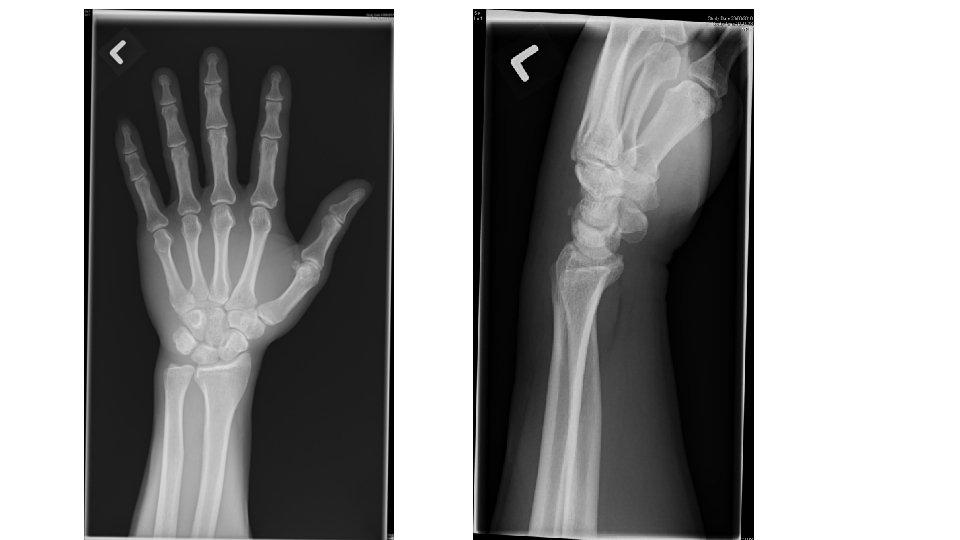

Q 2 • A 55 years old gentleman presented to AED due to fall with out stretched left hand. He complained left wrist pain and decreased range of movement over the left wrist. Physical examination showed tenderness along the ulnar border of the left wrist. X-ray of the left wrist was taken.

• What is the x-ray finding? And what is the diagnosis? • What is the mechanism of injury? • What is the indication for surgical intervention? Give 4. • What is the non-surgical management?

Avulsion fracture of triquetrum • Lateral view of the wrist x-ray • Small radiodense fragment just dorsal to the proximal row of carpal bones • Mechanism of injury • Typically occur from a fall onto an outstretched arm with the wrist in extension and ulnar deviation, or in extreme flexion • Avulsion fracture, usually off the dorsal radial surface account up to 93% of triquetrum # • Indication for surgery • • Open # Comminuted # Asso. nerve injury (ulnar n. ) Asso. vascular injury • Non-surgical management • Immobilization with short arm cast with the wrist placed in slight extension and the MCP joints free for 3 -6/52